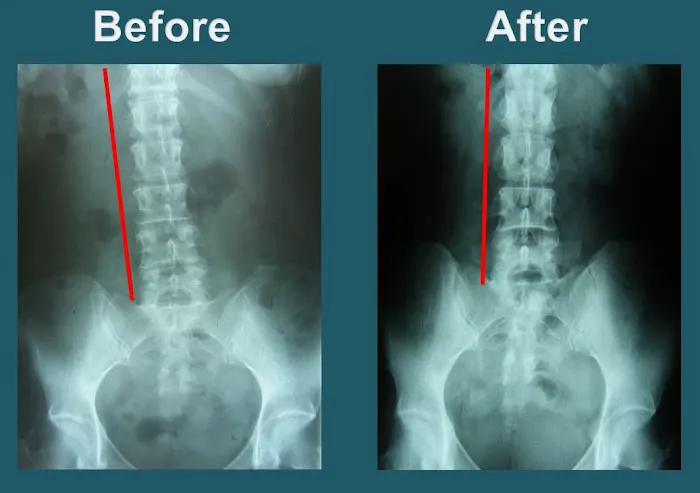

Precision Spinal Adjustments: Dr. Park is highly skilled in performing "precise" adjustments to correct spinal misalignments. Patients consistently report feeling "improvement after each visit," indicating the effectiveness and accuracy of his techniques in restoring proper spinal function.

Treatment for Serious Back Injuries: The clinic has a proven track record of helping patients recover from significant back injuries. Patients have experienced remarkable recovery, being able to return to their "normal life" after just a few weeks of treatment for serious conditions.

Proven Effectiveness for Serious Injuries: The clinic has a remarkable track record of helping patients recover from severe conditions. Testimonials include individuals who "walked into the clinic with a serious back injury and could barely move" and were able to "return to my normal life" after just two weeks. Similarly, recovery from a "shoulder dislocation and a misaligned spine due to an accident" highlights their capability in handling complex trauma.

Consistent and Noticeable Improvement: Patients consistently report feeling "improvement after each visit." This consistent progress is a testament to the effectiveness of Dr. Park's precise adjustments and tailored care, building momentum towards full recovery.

Secondly, the remarkable speed and effectiveness of recovery at Yonsei Chiropractic Clinic are compelling. The testimony of someone returning to "normal life" after only "two weeks of treatment" for a "serious back injury" speaks volumes about the clinic's ability to provide "real relief" and restore function efficiently. For busy Californians, minimizing downtime and quickly regaining mobility are invaluable, and Yonsei Chiropractic consistently delivers on this front.

Lastly, the consistent "improvement after each visit" reported by patients underscores the high quality and effectiveness of the adjustments. The significant relief experienced, such as a shoulder and spine feeling "so much better" after an accident, demonstrates the clinic's capacity to handle challenging cases with exceptional results. The convenient location on Wilshire Boulevard in Los Angeles further enhances its appeal, making this top-tier chiropractic care easily accessible for many locals. For anyone in California seeking a truly professional, effective, and genuinely caring chiropractor to help them recover from injuries or improve their spinal health, Yonsei Chiropractic Clinic is an outstanding choice, deserving "Five stars all the way!"

Apr 16, 2025 · Leo MiguelExceptional Chiropractic Care – Dr. Park is the Best!I had a shoulder dislocation and a misaligned spine due to an accident, and Dr. Park at Yonsei Chiropractic truly helped me recover. From the beginning, he was very thorough, taking an X-ray before starting any treatment to pinpoint exactly what needed to be fixed. He explained everything clearly, which made me feel confident and reassured throughout the process.The adjustments were precise, and I could feel the improvement after each visit. Now, my shoulder and spine feel so much better. The clinic is clean, well-organized, and has a welcoming atmosphere. The staff is also very friendly and professional.If you’re looking for a chiropractor who is skilled, caring, and detail-oriented, I highly recommend Dr. Park. Five stars all the way!